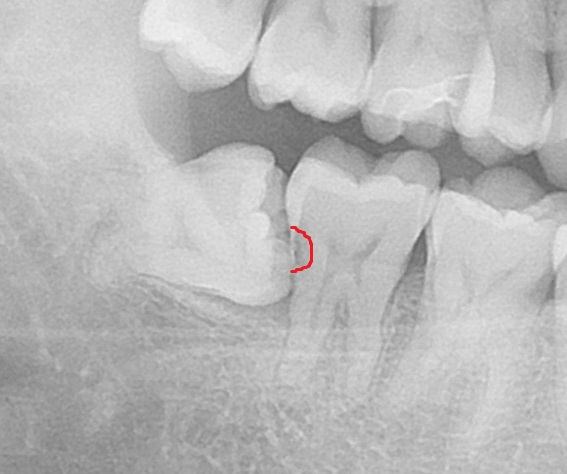

ここです。

ここが虫歯になっています。

1つ前のレントゲン写真と見比べると、赤枠の部分が黒く映っているのが分かりますね。

お口の中からは見えない部分なのですが、親知らずに物が詰まり、年月が経ち手前の歯を虫歯にしてしまいました。